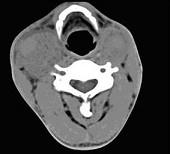

问题 男性,55岁,双侧颈部无痛性包块渐进性增大半年,行CT检查如图所示,请选择最佳答案 ( )

选项 A、双侧颈部肿大淋巴结 B、双侧血管瘤 C、双侧颈静脉瘤 D、双侧颈动脉夹层 E、双侧颈动脉瘤

答案 E